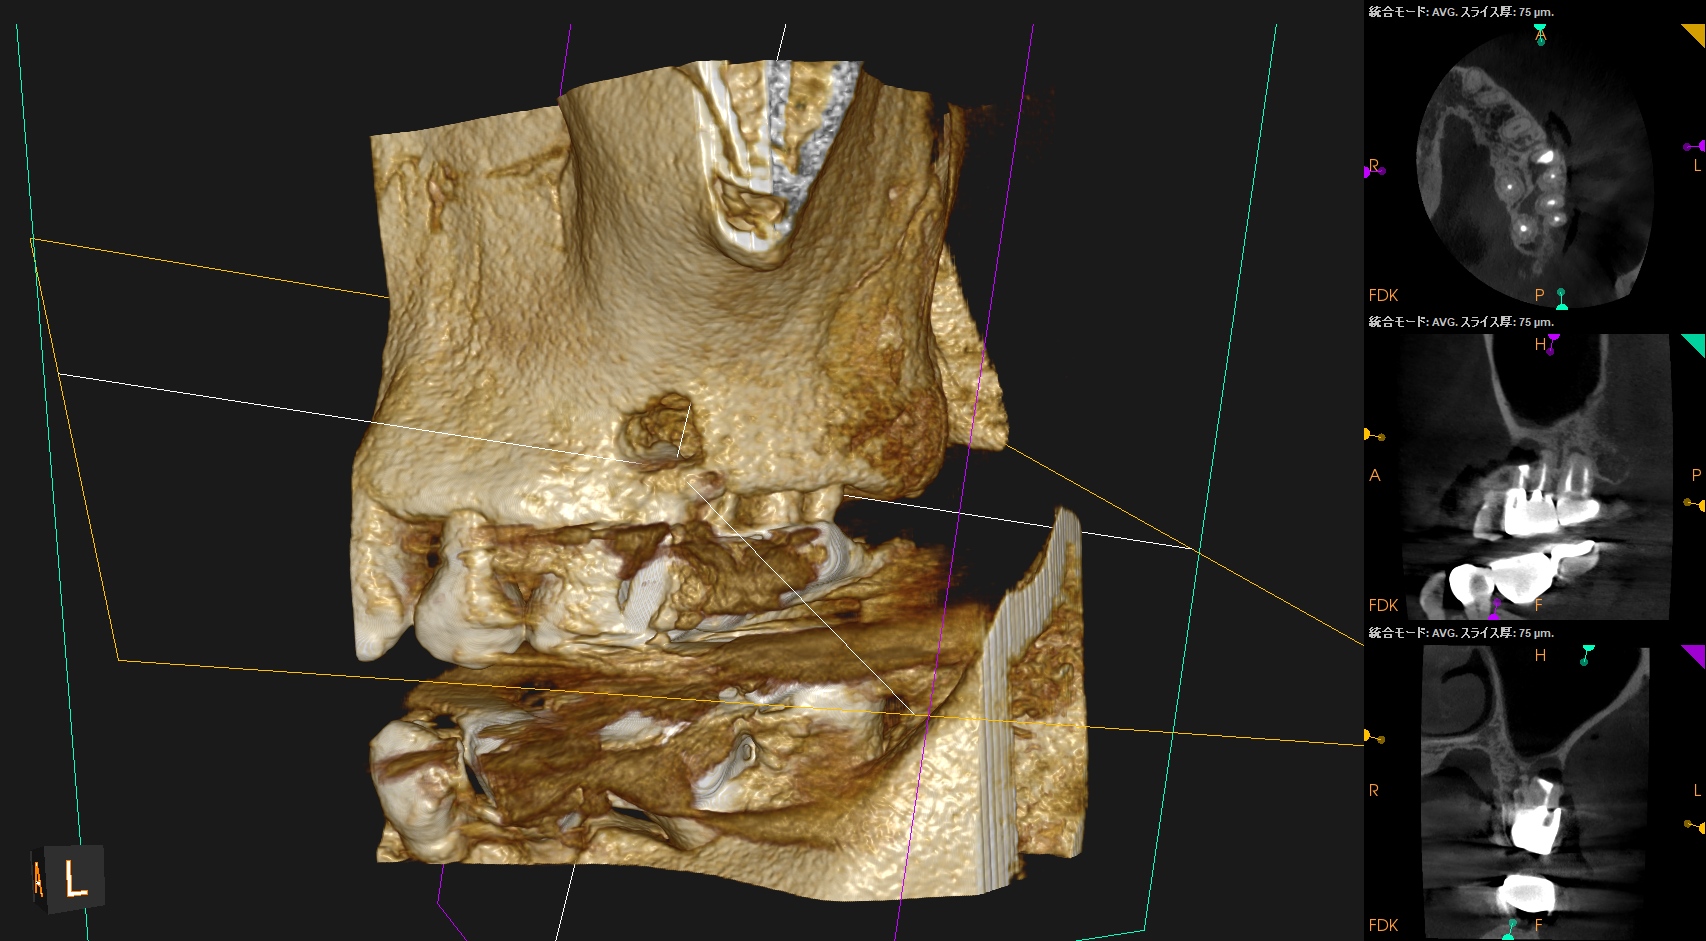

#14 MB Apicoectomy(2025.4.14)

MBのApexを発見した。

ここを3mm切断した。

Retroprep, Retrofillingした。

術後にPA, CBCTを撮影した。

逆根管充填材は逆根管形成で穿孔させたが即日修復=充填しているので問題ないだろう。